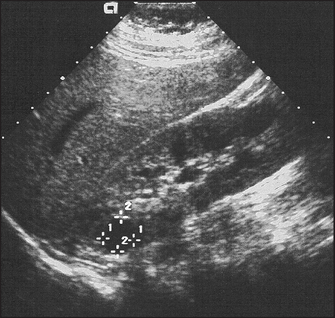

5. Ultrasound to look at renal size and for any renal mass or urinary obstruction (ureters and bladder); and by arterial Doppler to measure renal blood supply. Ultrasound of the scrotum is used to identify scrotal masses. Note the kidneys are usually both small on ultrasound in chronic kidney disease, but the exceptions include diabetes mellitus and amyloid or polycystic kidneys.

Figure 19.5 Ultrasound of polycystic kidneys. There are multiple discrete cysts, the largest 1.2 × 1.2 centimetres. (From Kaplan BS, Meyers K. Paediatric nephrology and urology: requisites, 1st edn. Mosby, 2004.)